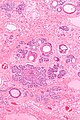

Trichoepithelioma. H&E stain. | |

| LM | typically well-circumscribed cell nest in the superficial dermis, surrounding by a fibrous stroma, basaloid cells - usu. with peripheral palisading +/-surround keratin-filled cysts, fibroblasts-like cell aggregate, similar to a follicular papillae (papillary-mesenchymal body) |

- Well-circumscribed cell nest in the superficial dermis.

- Surrounding by a fibrous stroma.

- Basaloid cells with peripheral palisading.

- +/-Surround keratin-filled cysts.

- Fibroblasts-like cell aggregate, similar to a follicular papillae (papillary-mesenchymal body).

The sections show well-circumscribed dermal nests of basaloid cells with peripheral palisading surrounded by a dense fibrous stroma. There is no artefactual clefting between the stroma and basaloid cell nests. Mitotic activity is minimal. Smaller hyperchromatic spindled-to-epithelioid cells in clusters (papillary-mesenchymal bodies) are found within the basaloid cells nests.